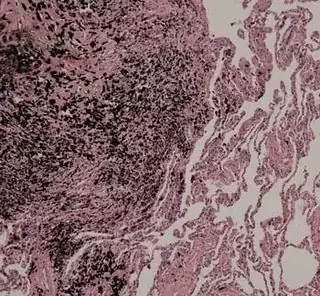

We've probably all seen photos of smokers' lungs compared to non-smokers lungs. For example:

However, I find it surprising that I can't find compelling evidence to prove the blogger is wrong. I can find no credible sources confirming the black appearance of smokers' lungs, and all the photos I can find are the same small set of images recycled so many times it's impossible to know where they came from originally. I've also confirmed that it's true that smokers are accepted as lung donors, and it seems difficult to believe that would be the case if they were routinely as grossly damaged as they appear to be in these images.

So my question is: Are smokers' lungs visibly and routinely blackened and/or discolored in the absence of lung disease?